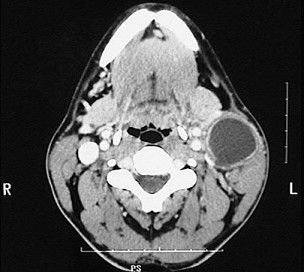

2.组图为牙瘤的外观及X 线表现,有关此病的描述错误的是 ( )![]() ![]() |